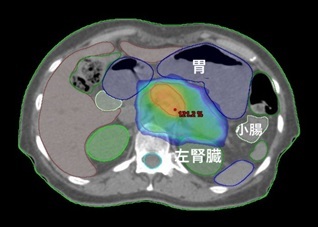

膵がん

切除可能な場合、手術が標準療法です。手術での取り残しを防ぐため、手術前に薬物療法を併用した放射線治療を行うことがあります。照射線量は40~50Gy、照射期間は3~6週間です。

高齢であったり心臓や肺の機能が悪くて手術ができない場合、あるいは手術で取り切れないと判断される場合は根治を目指した放射線治療を行うことがあります。照射線量は48-66Gy、照射期間は3~7週間です。

粒子線治療が望ましい場合は実施施設を紹介致します。

放射線治療に際し消化器内科あるいは外科の診察が必要です。

手術で取り残す可能性が高い箇所を中心にIMRTで照射。

胃や小腸、腎臓など周囲の臓器を避けて照射している。